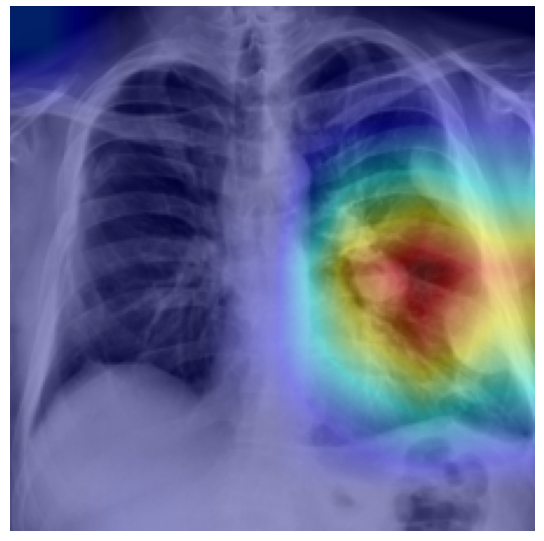

IV-E Interpretable Uncertainty via Ensemble GradCAM

To enhance clinical trust and transparency, Ensemble Grad-CAM visualization was implemented. This technique generates attribution heatmaps showing the regions of the chest X-ray image that contributed most strongly to the ensemble’s final prediction for a specific pathology.

Refer to caption

Figure 4: Example Ensemble Grad-CAM Visualization for Mass disease prediction

Crucially, individual Grad-CAM heatmaps are computed for each of the 9 ensemble members and then averaged to produce a stable, consensus driven ensemble visualization. This collective attribution provides greater reliability than a single model Grad-CAM output. The visualization focuses on classes where the final ensemble prediction probability exceeds 0.5, highlighting regions relevant to high confidence diagnoses. This capability allows clinicians to interpret which anatomical structures the diverse set of models focused on, and in cases of high Epistemic Uncertainty, enables visual comparison of attention patterns to understand where and why models disagreed on feature relevance.